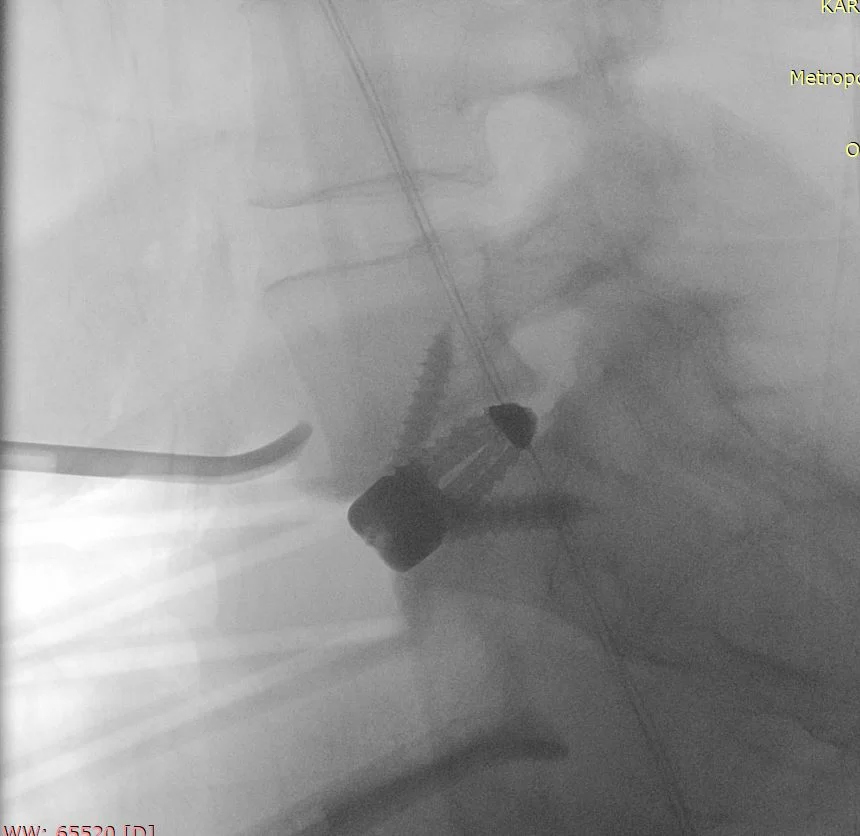

Οι σύγχρονες τεχνικές και η τεχνολογία επιτρέπουν πλέον η σπονδυλοδεσία να πραγματοποιείται με πολύ μικρές τομές και ελάχιστο τραύμα (και κατ’ επέκταση πόνο) για τον ασθενή. Η πιο σύγχρονη μέθοδος είναι η διαδερμική σπονδυλοδεσία με νευροπλοηγό (Εικόνες 4 – 6). Στην τεχνική αυτή, οι βίδες και οι ράβδοι τοποθετούνται μέσα από πολύ μικρές τομές και με τη βοήθεια της 3D-νευροπλοήγησης τα μοσχεύματα μπορούν να τοποθετηθούν με εξαιρετική ακρίβεια.